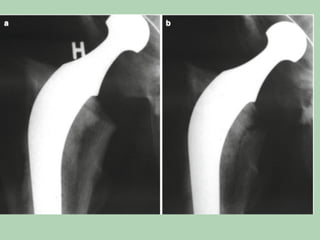

Prosthe*c	Joint	Infec*ons

•  A	prosthe*c	joint	infec*on	(PJI)	is	any

infec*on	due	to	bacteria	or	fungi	in	a	total	or

hemi-arthroplasty.

•  Classifica*on:

– Stage	I	infec*on	(acute	infec*on)

– Stage	II	(delayed	infec*on)

– Stage	III	presents	as	a	haematogenous

•  acute	PJI	becomes	chronic	a^er	few	weeks

– Stage	I	PJI:	An	acute	post-opera*ve	infec*on	that

occurs	<4	weeks	a^er	implanta*on.

– Stage	II	PJI:	A	chronic	infec*on	that	occurs	>4

weeks	a^er	implanta*on.

– Stage	III	PJI:	A	haematogenous	infec*on.